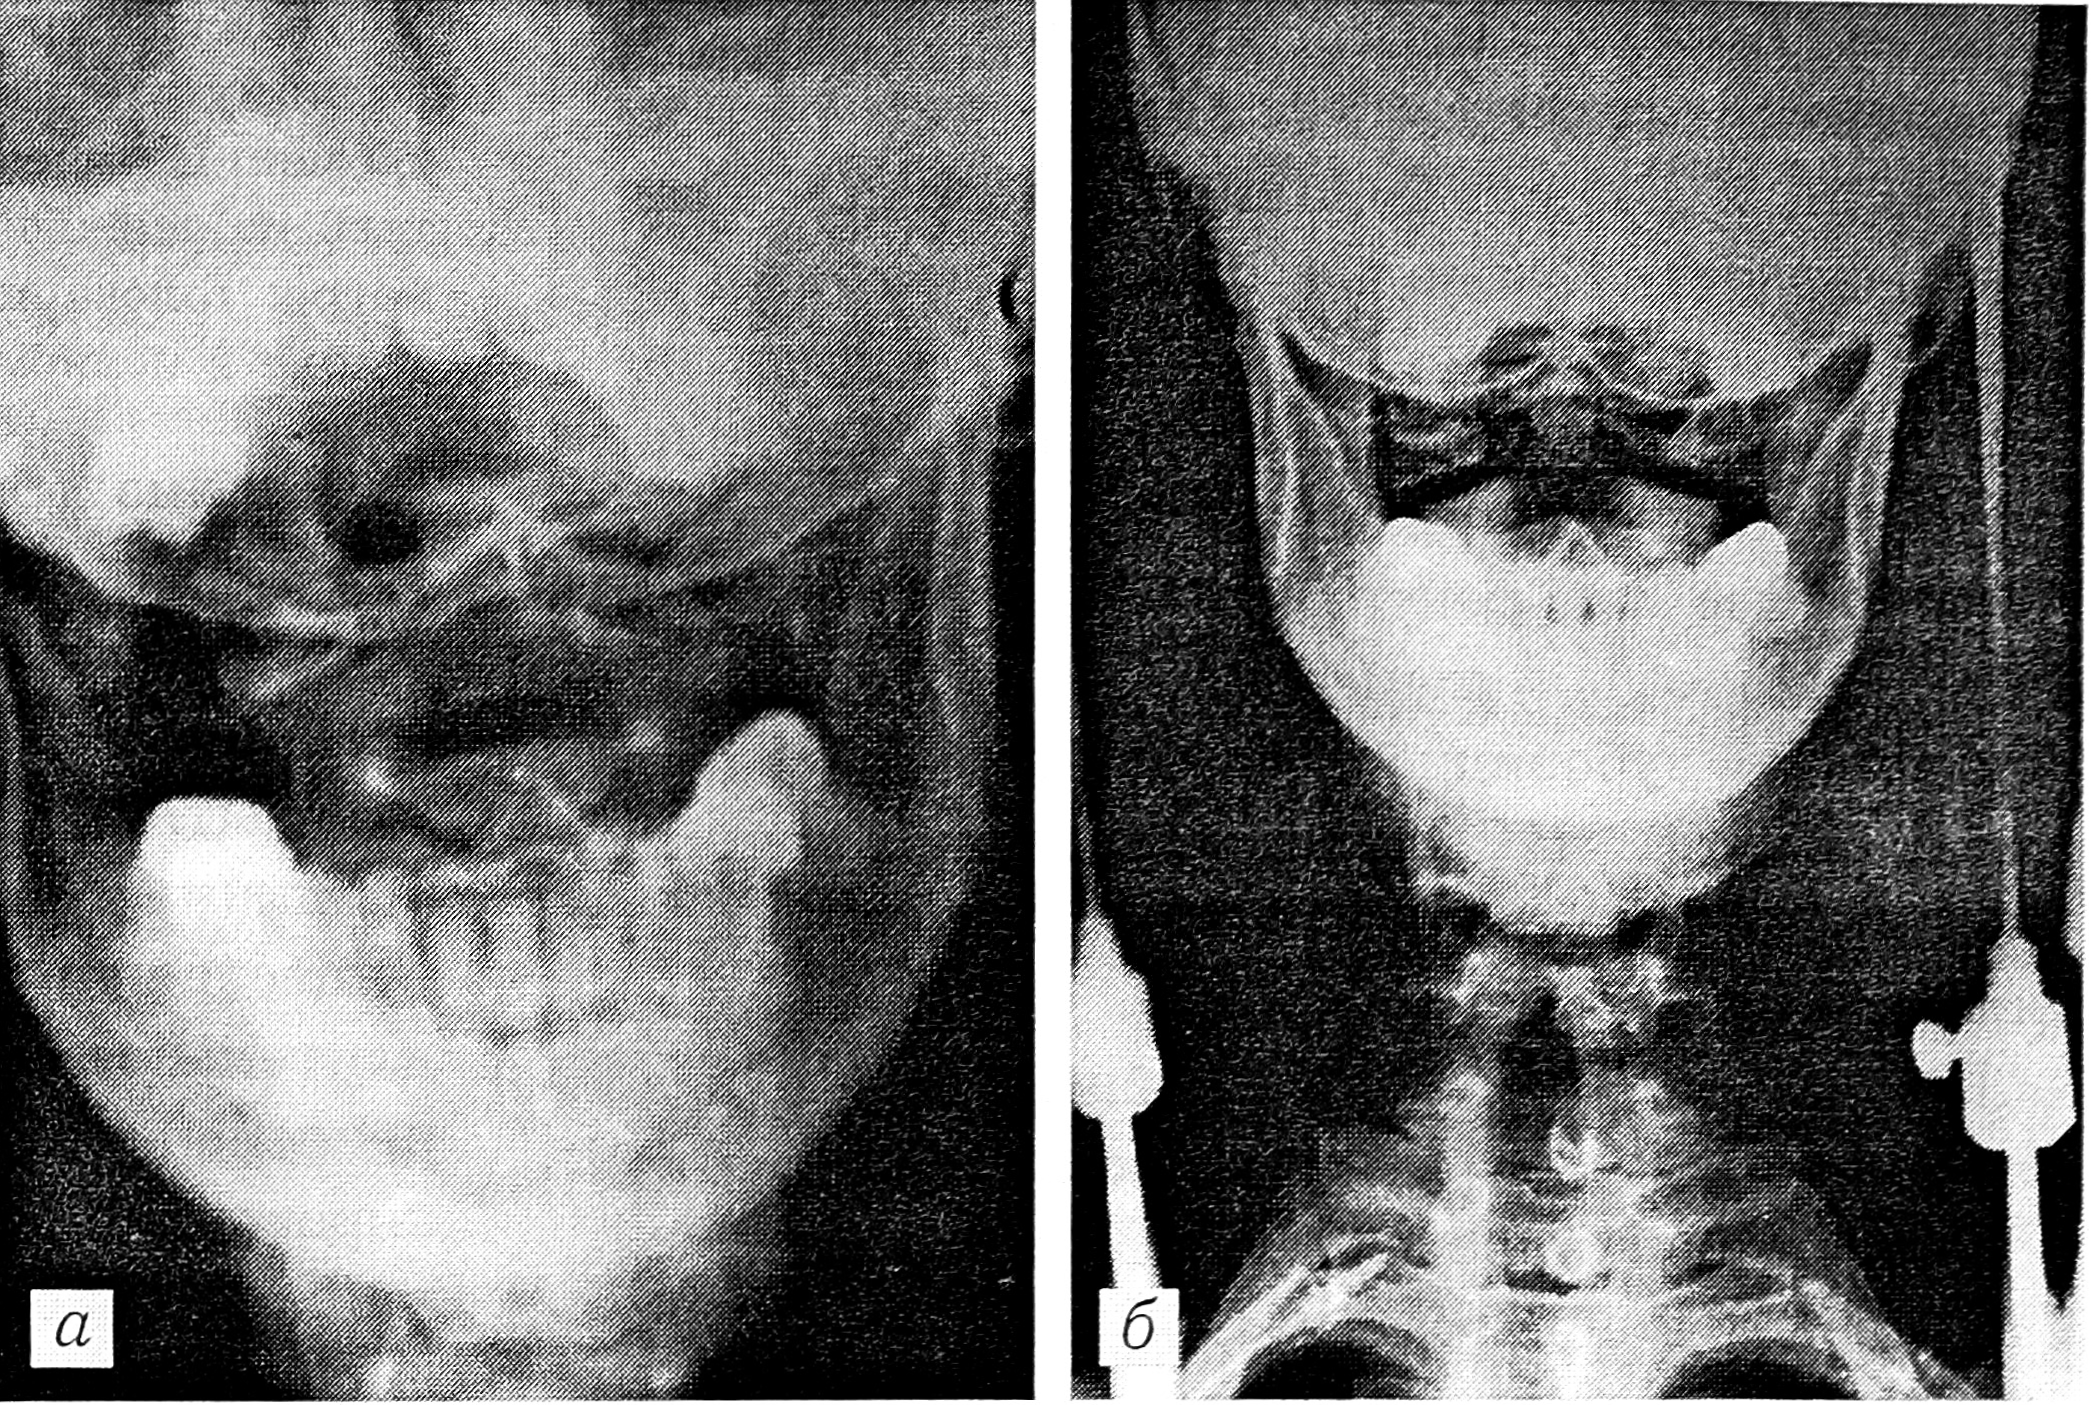

В отделении патологии позвоночника выполнены рентгенография (рис. 1, а), компьютерная томография. У больного отмечался грубый спастический тетрапарез, он с трудом мог передвигаться. Был наложен гало-аппарат, в котором достигнута полная репозиция (рис. 1, б). Явления тетрапареза быстро регрессировали. Гало-аппарат снят через 3 мес, шейный отдел фиксирован головодержателем из вспененного полиэтилена. Через 1 мес выполнена контрольная рентгенография, установлено сращение перелома. На функциональных снимках нестабильности не выявлено.

Рис. 1. Рентгенограммы больного П.

a — при поступлении: определяется переломовывих С2 позвонка; б — устранение переломовывиха в гало-аппарате: достигнута хорошая репозиция.